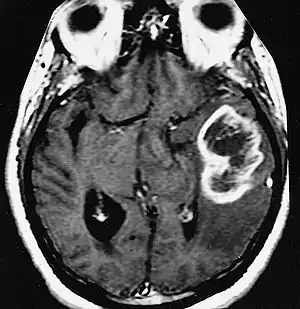

| An example of a ring-enhancement around a lesion in gliobastoma. In tumefactive multiple sclerosis, the ring-enhancement is open, not forming a complete ring. | |

These atypical lesion characteristics include a large intracranial lesion of size greater than 2.0 cm with a mass effect, edema and an open ring enhancement. A mass effect is the effect of a mass on its surroundings, for example, exerting pressure on the surrounding brain matter. Edema is the build-up of fluid within the brain tissue. Usually, the ring enhancement is directed toward the cortical surface.[2] The tumefactive lesion may mimic a malignant glioma or cerebral abscess causing complications during the diagnosis of tumefactive MS. T2-hypointense rim and incomplete ring enhancement of the lesions on post-gadolinium T1- weighted imaging on brain MRI enable accurate diagnosis of TDL[3]

Diagnosis of tumefactive MS is commonly carried out using magnetic resonance imaging (MRI) and proton MR spectroscopy (H-MRS). Diagnosis is difficult as tumefactive MS may mimic the clinical and MRI characteristics of a glioma or a cerebral abscess. However, as compared to tumors and abscesses, tumefactive lesions have an open-ring enhancement as opposed to a complete ring enhancement.[1] Even with this information, multiple imaging technologies have to be used together with biochemical tests for accurate diagnosis of tumefactive MS.[36]